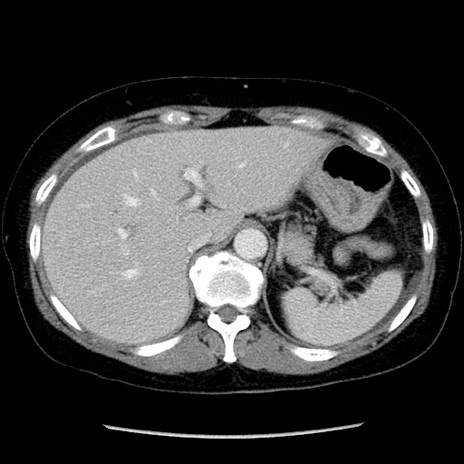

症例6(横断像)

【症例】50歳代女性

【主訴】下腹部痛

【現病歴】本日朝より下痢2回あり。 昼食を食べた後、嘔吐3回、下腹部痛認め、症状軽快せず、当院救急搬送。

最終食事:本日昼(生ものなし)。 昨日の夜、刺身を食ぺたとのこと。周囲に同様の症状の者なし。普段、排便は毎日あるとのこと。

【既往歴】卵巣癌術後(8年前に当院で卵巣摘出)

【身体所見】 意識清明、腹部:平坦、腸蠕動音→、やや硬、下腹部自発痛・圧痛あり、反跳痛あり、筋性防御なし。

【データ】WBC 16000、CRP 0.01